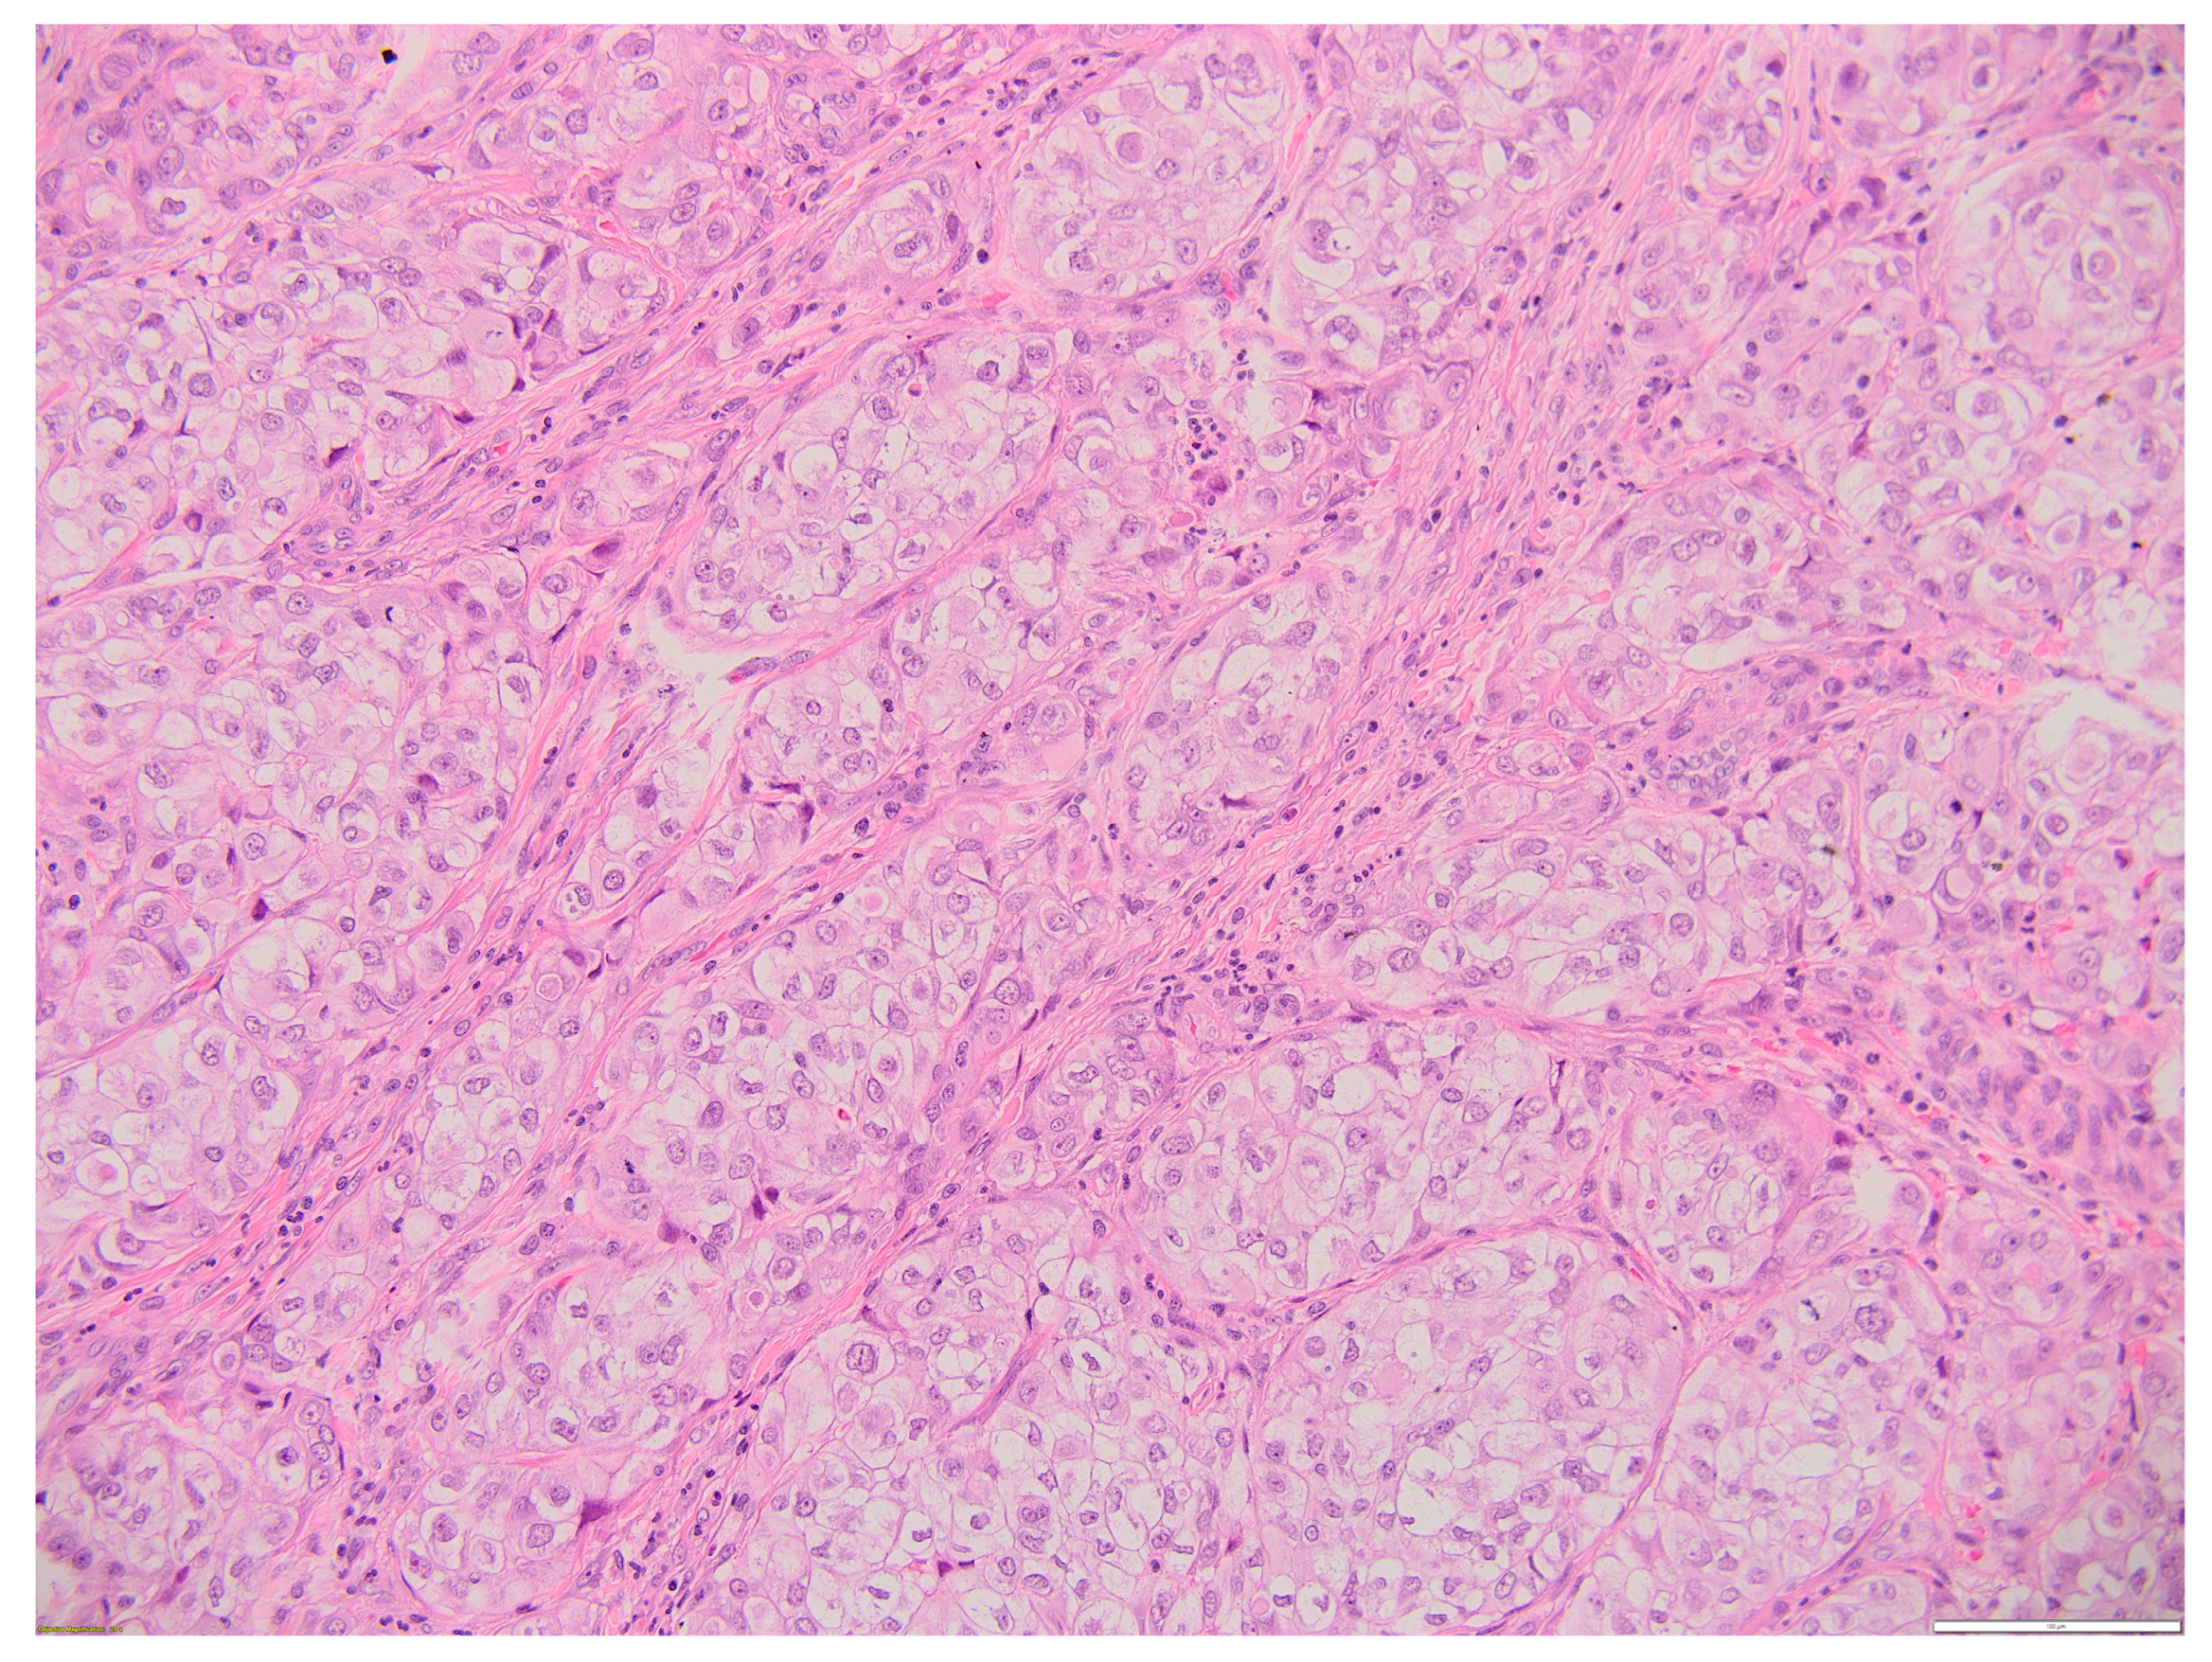

Following an assessment of the case as a multidisciplinary team, the patient was referred to the Surgery Department, where an excisional biopsy was performed from one of the left laterocervical adenopathies (a tissular fragment of 13/12/10 mm). Histological examination showed malignant infiltration with oval, round, and polygonal medium-sized cells arranged in a nest-like and islet-like growth pattern, findings consistent with metastasis. In order to establish the origin of malignancy, immunohistochemistry tests were performed, with CK19, p63, TTF1, and PAX8 being diffusely positive and thyroglobulin, Chromogranin A, Synaptophysin being negative in the tumor cells, thus proving the diagnosis of metastasis from primary mucoepidermoid carcinoma of the thyroid. CD5 staining was also performed in order to exclude primary metastatic thyroid lymphoma, and it was negative. Ki67 was positive in approximately 15% of tumoral cells.

Figure 5.

Thyroid MEC metastasis HE 20×. Oval, round, and polygonal cells arranged in a nest-like and islet-like growth pattern. Scale bar 100 µm.